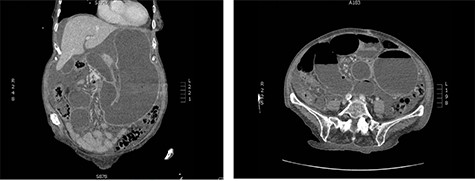

CASE DESCRIPTION

CT abdomen and pelvis on presentation; swirling of the SMA, markedly distended stomach and small intestine are noted.